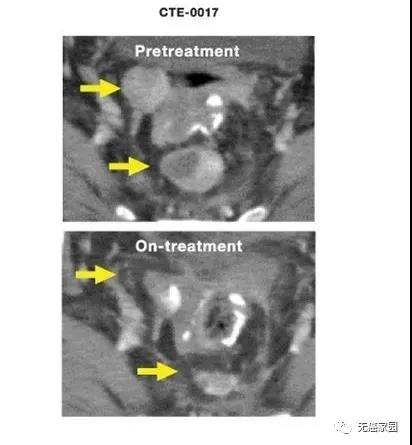

ilixadencel(伊利沙定)是一款同种异体树突状细胞(DC)疫苗。根据最新的全球性II期MERECA临床试验(NCT02432846)数据显示,ilixadencel联合靶向抗癌药舒尼替尼(索坦,通用名:sunitinib)一线治疗新诊断的晚期转移性肾细胞癌(mRCC)患者,与单独采用舒尼替尼治疗的患者相比,总缓解率提高一倍,完全缓解率更高,缓解更加持久!

今年5月,美国食品和药物管理局(FDA)授予了ilixadencel再生医学先进疗法(RMAT)资格。此次RMAT资格认定,基于今年2月公布的MERECA研究结果。数据显示,与术后舒尼替尼治疗相比,术前瘤内注射ilixadencel联合术后舒尼替尼治疗:存活率提高(54% vs 37%)、确认的总缓解率(ORR)提高一倍(42.4% vs 24.0%)、完全缓解率更高(6.7% vs 0%)、缓解时间更加持久(7.1个月 vs 2.9个月)。